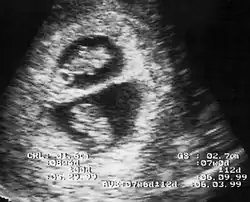

En France, selon les recommandations de la HAS de 2009, révisées en 2016[8], le diagnostic de grossesse gémellaire est effectuée lors de l'échographie du premier trimestre. Cet examen doit déterminer aussi la chorionicité, car elle devient de plus en plus difficile à préciser avec l'évolution de la grossesse. Ce premier examen permet de distinguer les grossesses bichoriales de bon pronostic, et les grossesses monochoriales, plus à risques de complications. Chacun des jumeaux doit être suivi selon les examens réalisés habituellement lors d'une grossesse unique (par exemple : dépistages d'un retard de croissance intra-utérin, d'une trisomie 21, de malformations...)[6].

La fréquence des échographies varie selon le niveau de risques de la grossesse gémellaire, de une par mois à une par semaine. La détermination des risques au dernier trimestre peut influencer le choix de la date d'accouchement[9]

- ↑ Bernard Benoit, « Échographie des grossesses gémellaires », La Revue du Praticien, vol. 56, no 20 « Les jumeaux », , p. 2235-2236.